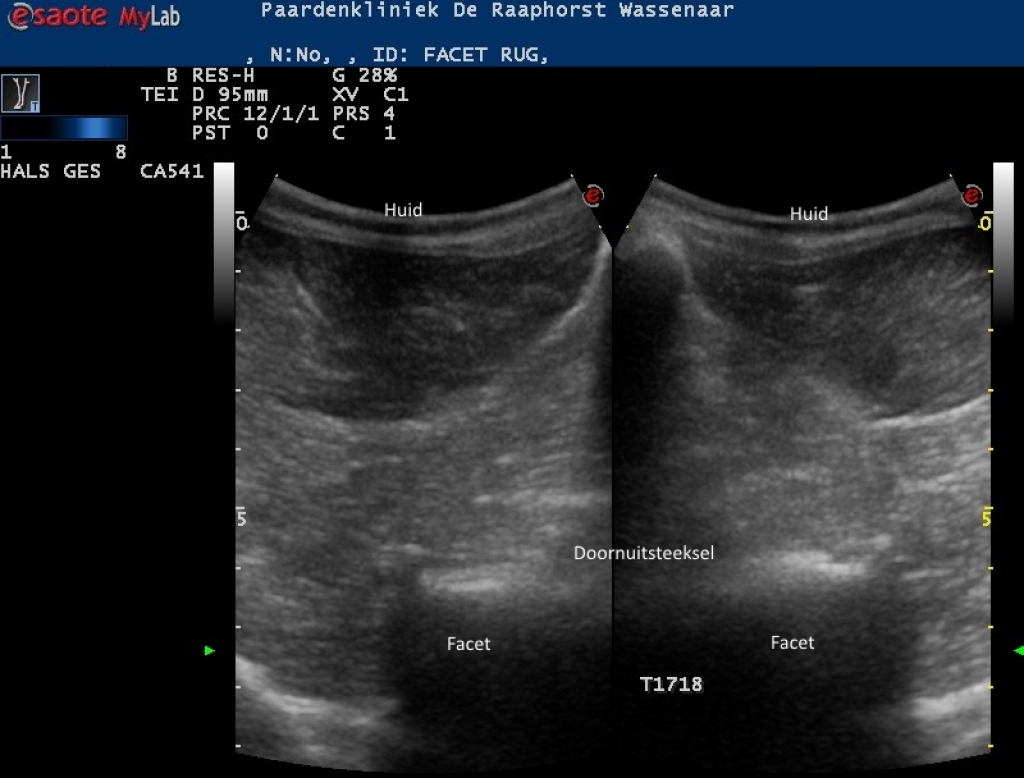

Links: Echografisch beeld van normale facetgewrichten van de borstwervels

Echografisch beeld van normale facetgewrichten van de borstwervels